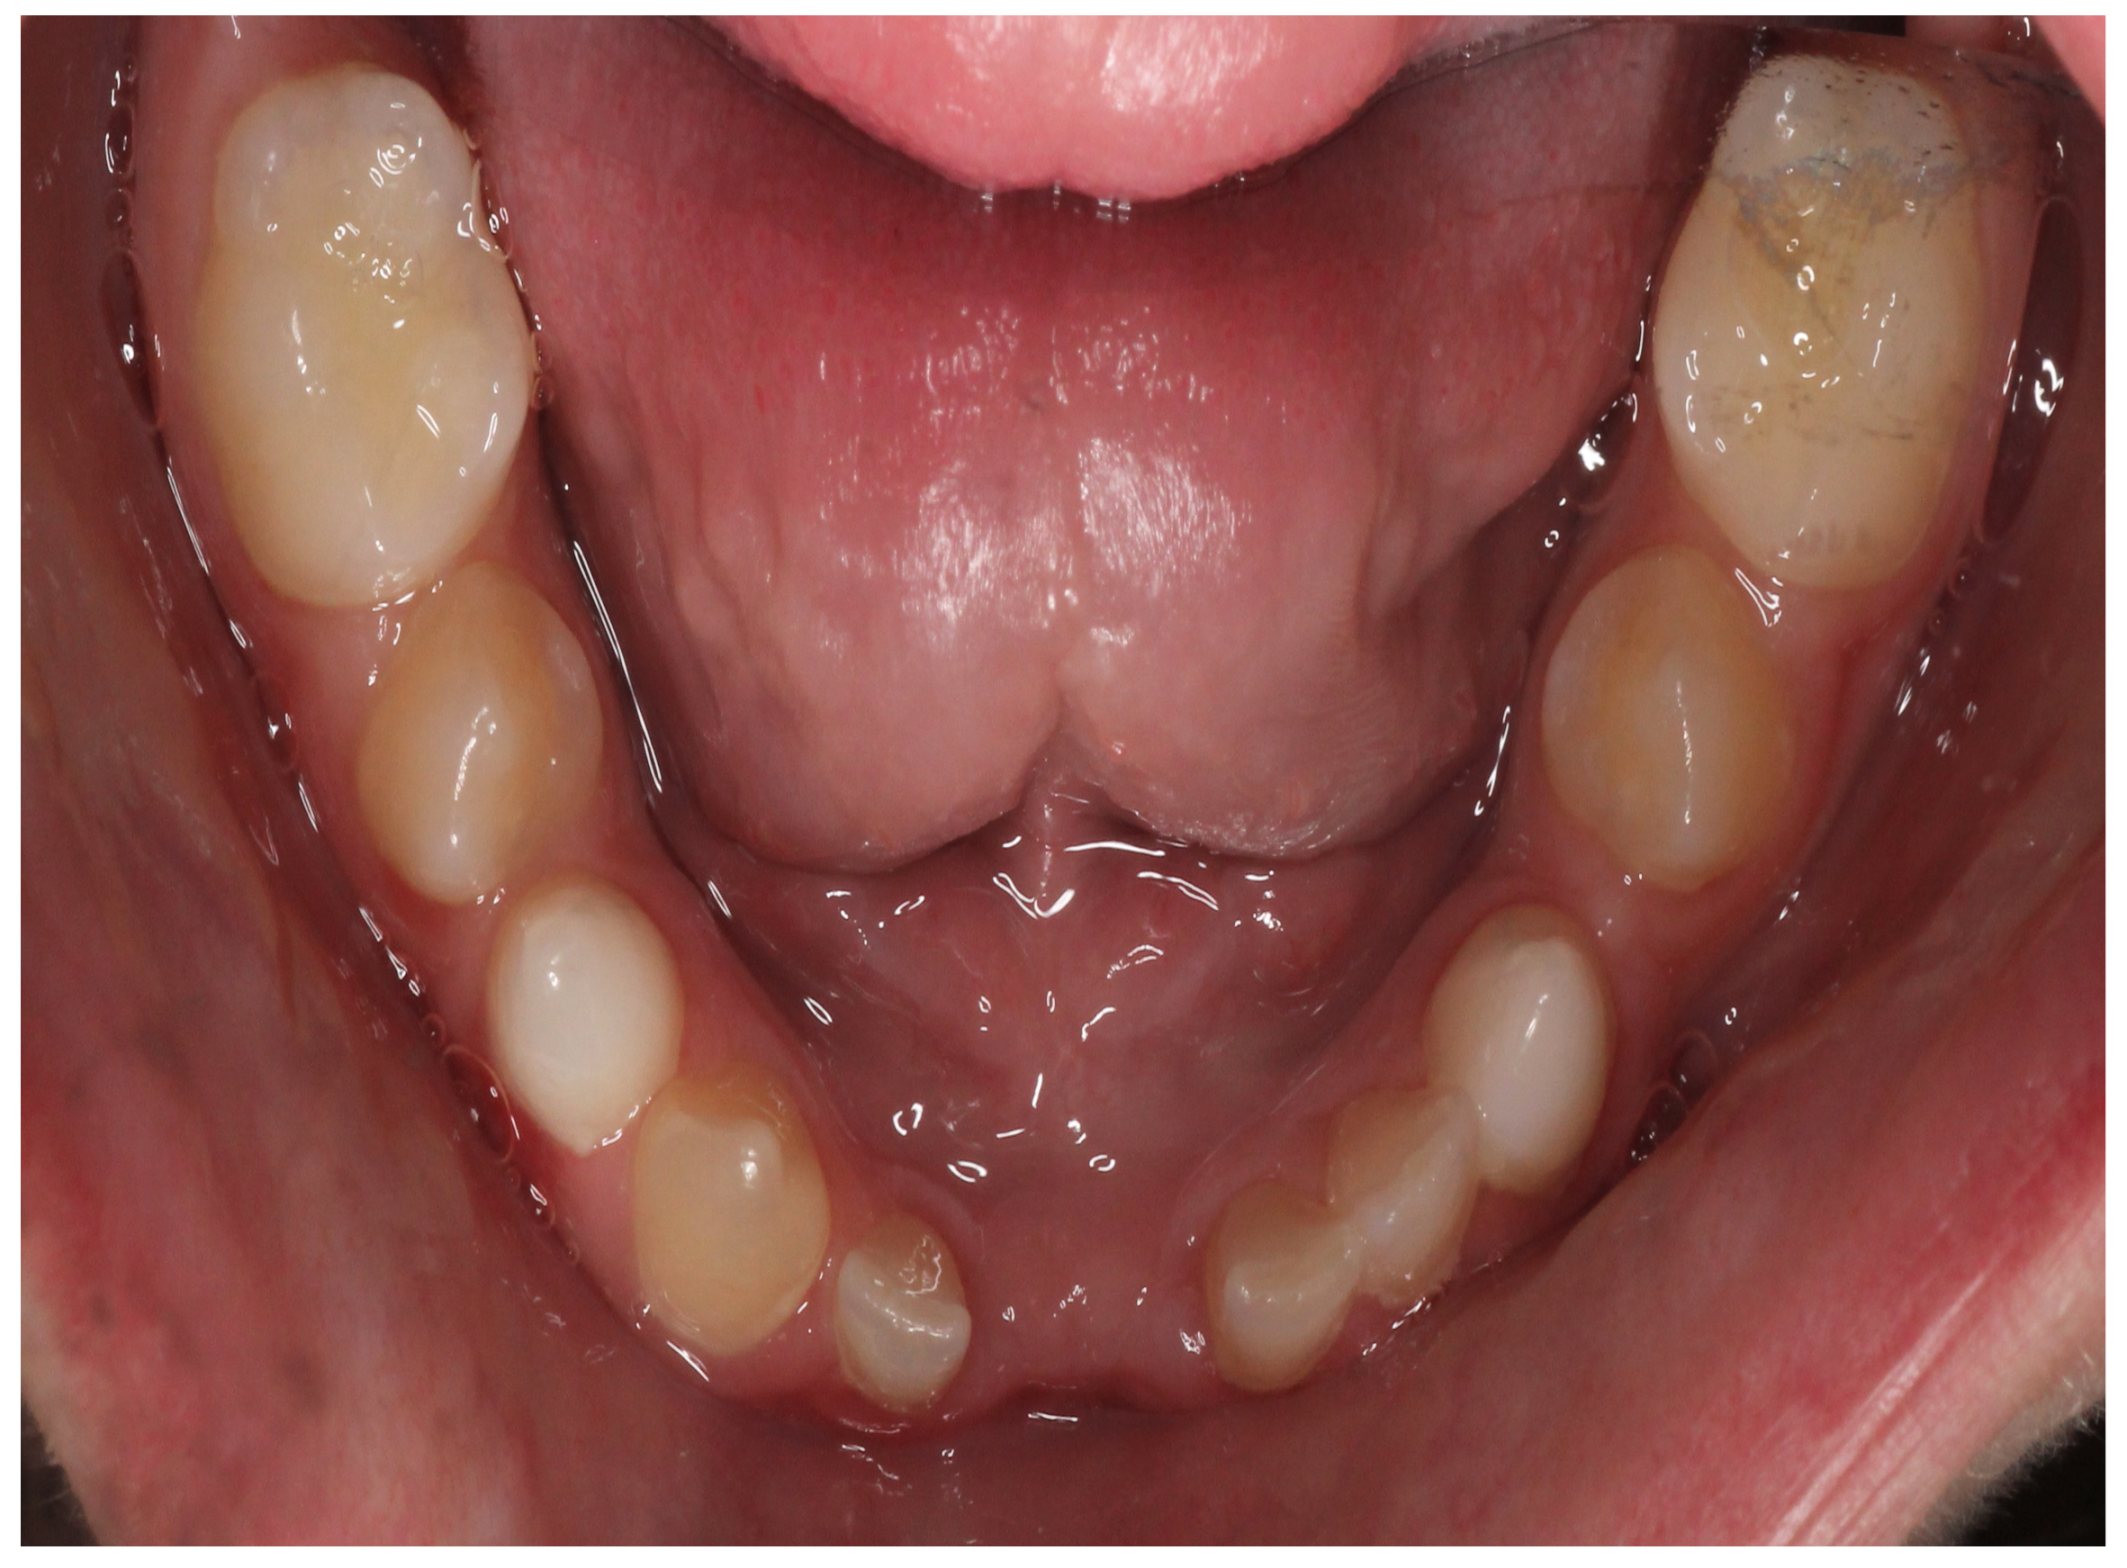

At the initial visit, the permanent teeth present were 15, 34, 33, and 44. The primary teeth present were 75, 72, 81, 82, and 85. Several dental anomalies were observed: The mandibular primary canines (73 and 83) were conical in shape, the maxillary right lateral incisor (12) was peg-shaped, and microdontia was noted in the maxillary central and lateral incisors (11, 21, and 22). Erosive wear was also evident on the maxillary primary molars and canines (54, 53, 63, and 64), suggesting the structural weakening of enamel (Figure 1, Figure 2 and Figure 3).

Figure 3. Intra-oral photograph of the lower arch.